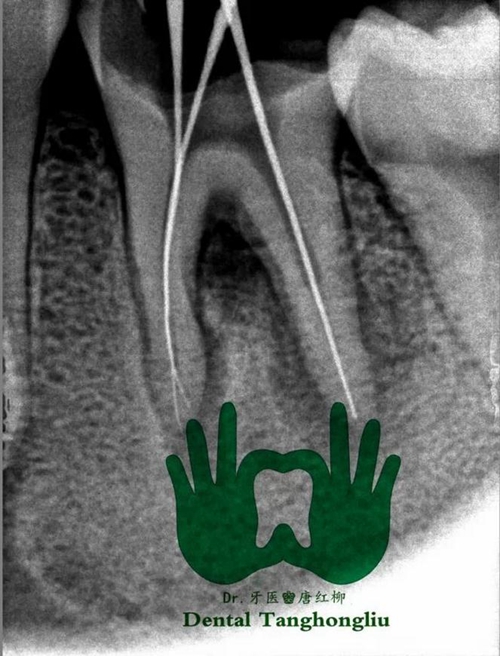

1、診斷問題。要詳細(xì)詢問主訴牙的既往史、現(xiàn)病史,做出更確切的診斷,不要忽略其一,做到有所為,有所不為。比如本是中深齲中的可復(fù)性牙髓炎,需先進(jìn)行安撫后再充填,不宜一次性充填。需對(duì)癥下藥,不要抱有僥幸的心理。

2、備洞問題。診斷已有確切,接下來備洞。盡使用新的車針,并大量手機(jī)冷切水,間歇性去腐。操作輕柔,近髓處腐質(zhì)盡量使用慢機(jī)或小挖匙,盡減少備洞時(shí)溫度對(duì)牙髓的刺激因素,同時(shí)對(duì)于洞邊緣的無基釉或薄壁弱尖要有效的去除,預(yù)防白線和樹脂的塌陷而引起微滲漏。

在這,再分析一下納米滲漏問題。樹脂進(jìn)入牙本質(zhì)小管形成樹脂突并充滿管間的纖維網(wǎng),形成了機(jī)械的固位,但如果樹脂滲入不完全,在脫礦的牙本質(zhì)出現(xiàn)未滲入?yún)^(qū)域則是術(shù)后敏感的主要原因,這種缺陷會(huì)導(dǎo)致牙本質(zhì)封閉不良粘結(jié)界面的快速降解,繼發(fā)齲的產(chǎn)生,所以涂完粘結(jié)劑后不要馬上光照,要等候粘結(jié)劑的滲入,并給與微氣流吹,細(xì)微的加壓。而因?yàn)榧{米滲漏問題出現(xiàn)咬合痛,必須去凈原充填材料,并做預(yù)防性擴(kuò)展0.1-1.3mm左右,再充填。